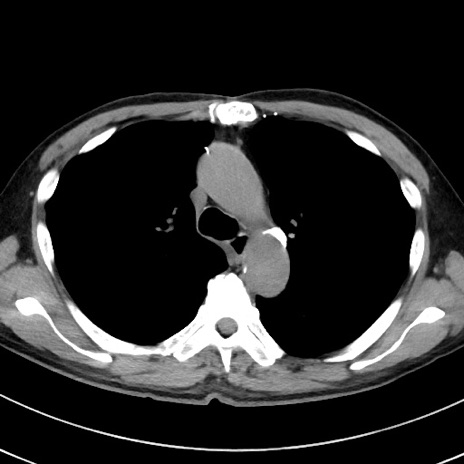

症例38(横断像)

【症例】70歳代 男性

【主訴】腹痛・嘔吐

【現病歴】昨晩より、嘔吐・腹痛あり。今朝になっても嘔吐あり。来院。

【既往歴】心臓バイパス手術、開腹胆摘、腸閉塞

【身体所見】BP 107/71mmHg、HR 116/min、腹部:平坦、軟、下腹部に軽度圧痛あり。反跳痛なし。

【データ】WBC 15100、CRP 0.32